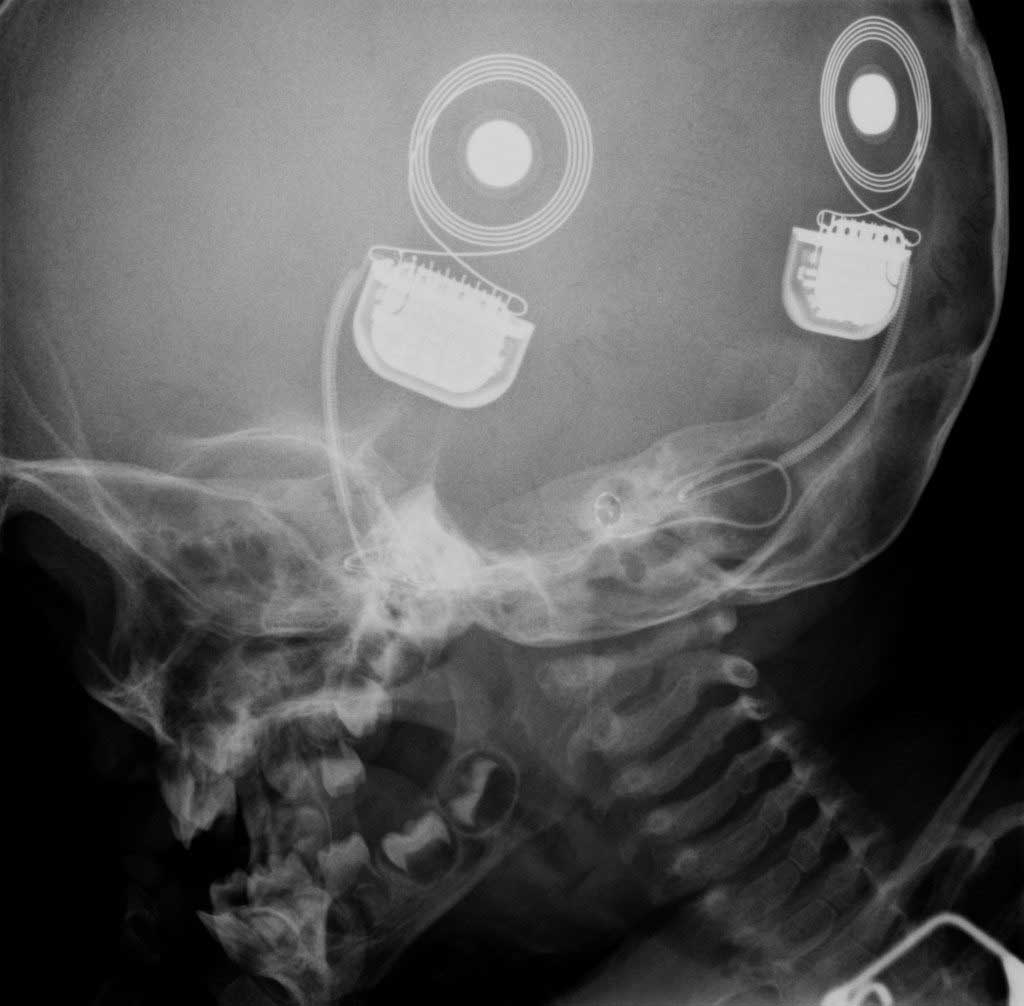

Wirklich fremd sind uns Implantate schon lange nicht mehr. Zahn-Implantate aus Quarz, Elfenbein und Holz gab es schon vor tausenden Jahren, Hörgeräte werden seit Jahrzehnten implantiert, Cochlea Implantate, die direkt mit dem Hirnstamm interagieren sind bereits in Verwendung. Warum empfinden wir den Bruch der Mensch-Maschine-Barriere trotzdem noch als zu weit hergeholt?

Implantismus

Erstes Gehirn-Implantat beim Menschen